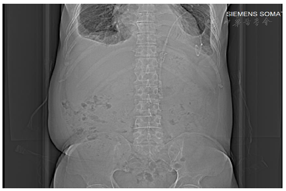

心脏超声:左室前间壁中间段心肌搏动略减弱,左室心尖部心肌搏动略减弱,大量心包积液,右室前壁受压塌陷,右房顶受压塌陷,下腔静脉回流障碍,主动脉瓣退行性变,主动脉瓣少量反流,主动脉硬化;EF:0.52。肺CT:双侧胸腔积液伴双肺下叶实变、膨胀不良。双肺散在斑点结节影。双肺慢性炎症。主动脉硬化,冠状动脉高密度,心包积液,心影增大。全腹部CT增强(图1):腹、盆腔积液、渗出改变;腹膜后多发渗出改变,腹盆壁渗出;双侧胸腔少量积液,双肺下叶受压膨胀不良,建议进一步详查;心影饱满,心包积液;左侧胸腔引流术后改变,请结合临床;慢性胆囊炎伴胆囊结;双肾体积明显增大,双肾盂扩张积水,双肾周多发渗出改变,双肾鞘增厚;左肾小结石或钙化灶;胃壁增厚,直肠壁增厚,建议结合镜检;骨盆骨质密度略不均。